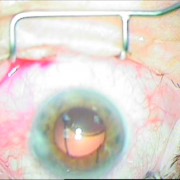

ΙΚ1 ΜΙΚΡΗ ΚΟΡΗ ΛΕΥΚΟΣ ΚΑΤΑΡΡΑΚΤΗΣ ΜΕ ΤΡΑΥΜΑΤΙΚΗ ΡΗΞΗ ΟΠ ΠΕΡΙΦΑΚΙΟΥ ΑΠΟ ΕΓΧΥΣΗ ΑΝΤΙVGEF ΠΑΡΑΓΟΝΤΑ

Μικρή κόρη λευκός

καταρράκτης με τραυματική

ρήξη οπ.περιφάκιου από

έγγχυση ANTIVGEF παράγοντα

ΕΝΘΕΣΗ ΔΙΑΣΤΟΛΕΑ ΙΡΙΔΟΣ

Ένθεση διαστολέα ίριδος